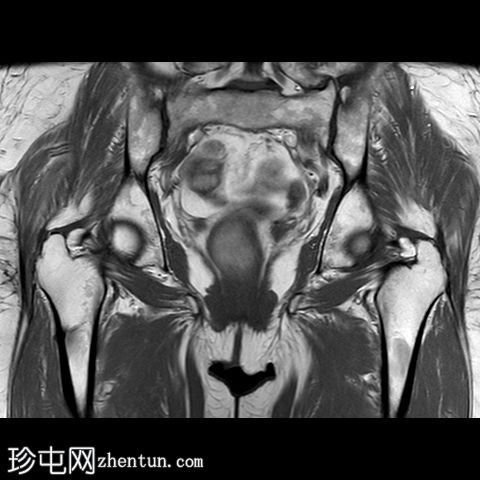

冠状位

T2

一条水平T1和T2低信号骨折线横断右股骨干外侧皮质。近1/3的骨干周长受累,并伴有邻近骨髓水肿。其余皮质骨完整。左股骨未见异常。